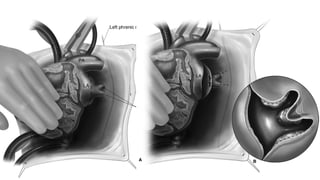

PRINCIPLES

• Principle

✦ On CPB or Circulatory arrest

✦ Identify 4 PV, common chamber and dissect and loop vertical vein

✦ Achieve wide tension free non obstructing anastomosis between common chamber and LA

✦ Avoiding purse stringing of suture line

✦ Divert all pulmonary venous blood to LA

✦ Close intra-atrial communication

★ Patch Material

• Pericardium

• Dacron ( Polyethylene terephthalate )

✦ Ligate vertical vein close to insertion into systemic vein

SC - TAPVC - POSTERIOR

APPROACHPaul Ebert